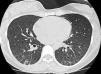

Upon physical examination, the patient presented no fever, tachycardia (140bpm), tachypnea (36 breaths per minute) and baseline oxygen saturation (breathing room air) of 91%. Lung auscultation showed preserved vesicular murmur with bibasilar crackles. Blood workup revealed normal ionogram, C-reactive protein 80g/dl, leukocytes 11430mm3 (90% neutrophils and 1.4% eosinophils), hemoglobin 12.4g/dl, hematocrits 36.4%, platelets 309000mm3. Baseline arterial blood gas analysis reported pH 7.44, pCO2 31mmHg, pO2 54mmHg, CO3H 21.1mmol/L. Chest radiography showed a bilateral micronodular pattern in both lung bases associated with mild fissure thickening. Diagnostic bronchoscopy demonstrated no endobronchial lesions, and samples were taken from the bronchoalveolar lavage and aspirate as well as a transbronchial biopsy. In the lavage, a moderate number of lymphocytes were observed along with polymorphonuclear cells. No eosinophils were observed. The biopsy showed fragments of lung parenchyma with isolated non-necrotizing epithelioid granulomas and isolated giant cells situated at the septum. Histochemical stains for detection of acid-fast bacilli (Kin-Youn) were negative. The bronchial aspirate was also negative for malignancy. In three sputum culture samples, Mycobacterium avium was isolated and the pigeon precipitin study was negative. Thoracic tomography (HRCT) showed an interstitial pattern with diffuse bilateral centrilobular nodules, together with images of airway consolidation in the sloping parts of both bases, probably related with atelectasis, as well as pneumomediastinum related with the transbronchial biopsy. No mediastinal or axial pathologic lymphadenopathies were observed (see Fig. 1).